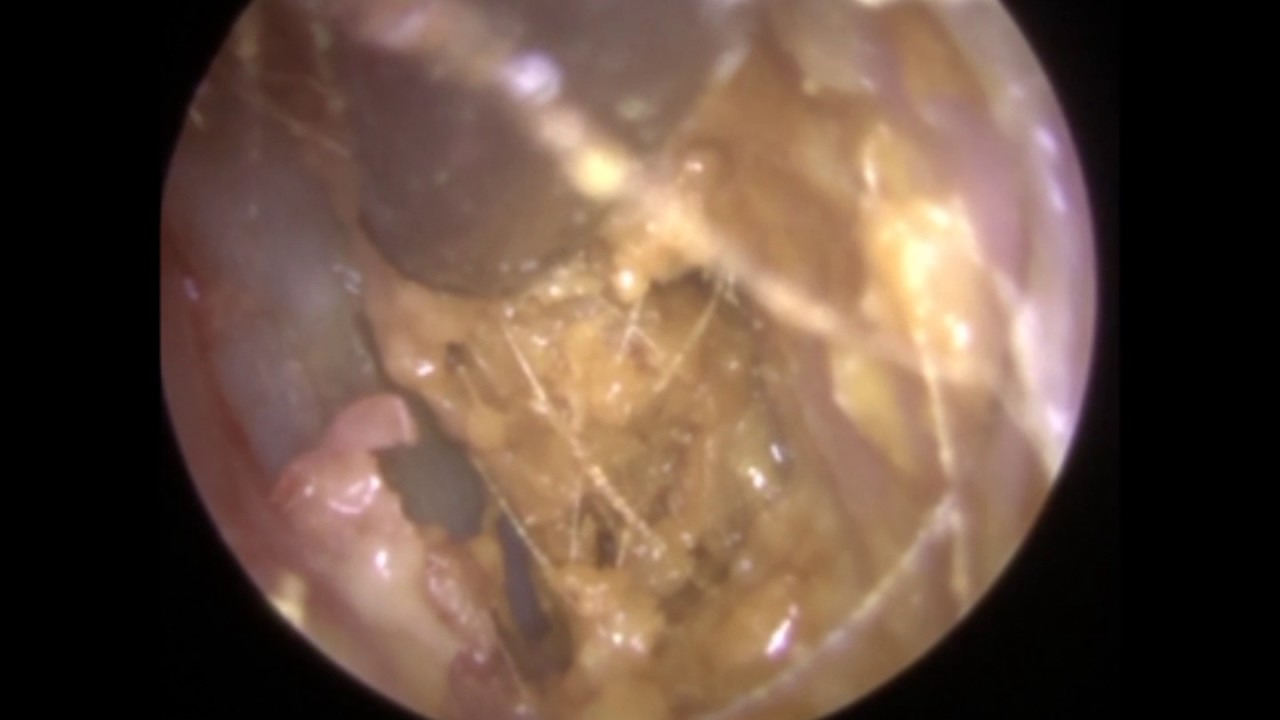

Huge Ear POLYP Discovered After Ear Wax Removal - Mr Neel Raithatha

ear polyp wax removal.